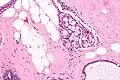

Collagenous spherulosis is characterized by a tubular/cribriform architecture with intratubular eosinophilic material that classically is arranged like the spokes of a wheel ("radial spikes"). There is usually no mitotic activity, and two cells populations (epithelial & myoepithelial) are present, like in benign breast glands.

The lesions are typically small (less than 50 spherules per lesion, less than 100 micrometers in size) and may be multifocal.

Intermed. mag.

High mag.